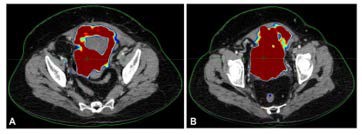

Figure 1: CT Images Showing Pelvic Mass Involving the Bladder near Uterine Wall

The CT image of Figure 1 demonstrates the presence of a soft tissue mass arising from the bladder wall and extending toward the uterine surface. These imaging findings supported the initial diagnosis and guided the decision to begin first-line chemotherapy. The patient underwent four cycles of Area Under the Curve (AUC2) gemcitabine + carboplatin chemotherapy. However, due to tumor progression, a therapeutic re-evaluation led to the administration of MVAC chemotherapy. Subsequent PET-CT scans showed further tumor growth (9.6 x 9.2 x 8.6 cm), necessitating radical anterior exenteration, including ileal conduit construction, radical cystectomy, and complete abdominal hysterectomy with bilateral salpingo-oophorectomy.